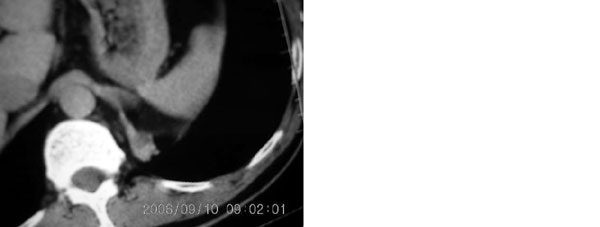

左下叶后基底段内胸主动脉旁可见一类梭形团块状影,边界较清楚,其内有小结节样高密度钙化影,肿块与胸主动脉可见条状影相连(见下图).

诊断:左下叶肺段隔离症.

把选定的图像复制到woad,左键双击--图片设计格式--图片--亮度,调整亮度(到60--70)即可见到病灶血管与降主动脉相连,即病灶由降主动脉供血.